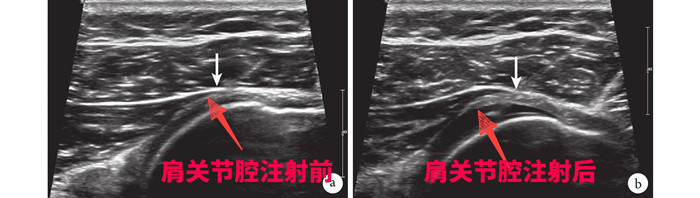

針對劉大爺?shù)那闆r,徐慧勝制定了個性化治療方案“體外沖擊波結(jié)合超聲引導(dǎo)下肩關(guān)節(jié)注射治療”,先采用沖擊波松解肩關(guān)節(jié)周圍黏連的組織,然后在超聲引導(dǎo)下將消炎鎮(zhèn)痛液準(zhǔn)確注射到肩關(guān)節(jié)腔、滑囊及神經(jīng)周圍,起到雙管齊下的作用。15分鐘后,劉大爺感覺疼痛減輕了大半,活動明顯改善。經(jīng)過3次治療,劉大爺?shù)募缰苎滓鸦局斡?